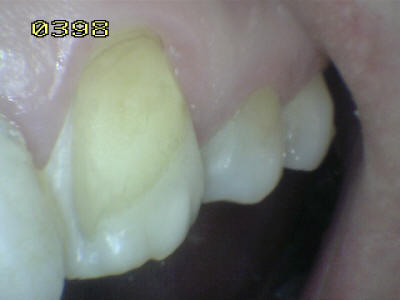

| Paciente de sexo femenino de 60 años de edad, que a la inspección

clínica se observa perdida de esmalte por erosión ácida en los dientes

antero-superiores. Durante el interrogatorio el paciente cuenta que

ingiere grandes cantidades de limón y naranjas naturales. Este habito

dietético ocasiona erosión ácida por el contenido de acido cítrico que

contienen dichas frutas. Note en las imágenes inferiores el deterioro

extenso del esmalte, que lleva en algunos sitios a la exposición de la

dentina. Como el proceso es gradual el paciente no tiene sintomatología

dolorosa al estímulo térmico.

Este tipo de lesión es clasificada en una escala de leve, moderada y

grave, como grave y debe ser tratada con recubrimientos estéticos

a base de resina o porcelana. El no tratar estas lesiones puene llevar a

producir caries dentinaria con la pérdida de las piezas dentales. Otra

acción a tener en cuenta es la posibilidad de un cambio en la

dieta, basado en la disminución de la frecuencia de la ingesta del limón

y naranja.

Observe como se ha perdido

la estructura dental en 13, 12 y en 11 una carilla en

resina compuesta donde se ha deteriorado el borde cavo

superficial de la misma. En 23 el mismo patrón de

desmineralización dental |